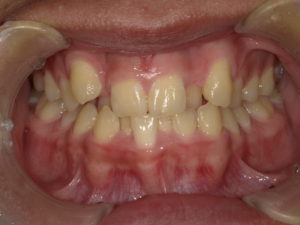

【悪い歯並び4】叢生(そうせい)

user comment….

叢生(そうせい)は、大きい歯があったり、顎が小さかったりして、歯の生えるスペースが狭くなってしまっている状態です。「乱ぐい歯」と呼ばれることもあります。

叢生は、歯が重なっている状態なので、歯磨きをしても汚れが残りやすいです。その結果、虫歯や歯周病などのトラブルに繋がる可能性があります。